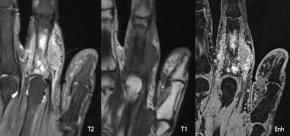

[Musculoskeletal [MS]] 83 Years/F, 2nd finger mass since 3 months ago, colon cancer history(+)

| Answer | Metastasis |